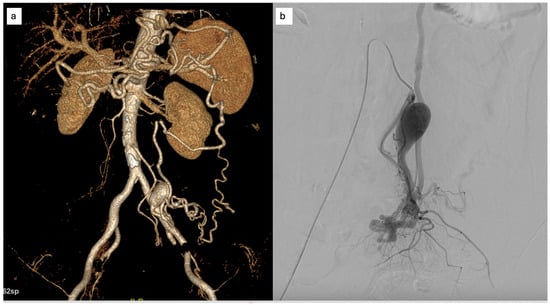

Contrast-enhanced CT imaging revealed tortuous mesenteric vessels arising from the IMA, associated with a small centromesenteric vascular nidus and early venous drainage into the sigmoid venous system. Perivisceral fat stranding and venous congestion of the sigmoid mesocolon were noted, raising suspicion for a hemodynamically significant AVM (Figure 5).

Figure 5. (a) CT volume rendering reconstruction showing a type II IMAVM, (b) transverse scan with evidence of the tortuous course of the afferent artery and the centromesenteric nidus; (c) CT showing signs of edematous perivisceral tissue (arrows).